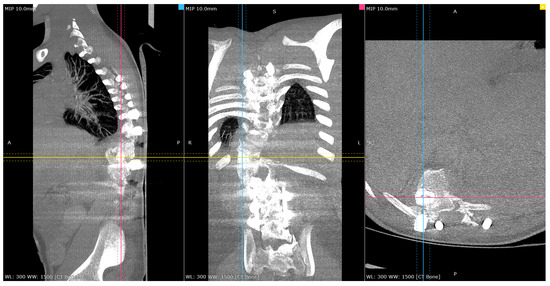

Figure 4.

Representative pre-op CT scan views of the congenital deformity. Cross-reference grid lines mark the intersection of the corresponding image planes: Blue—sagittal; Pink—Coronal; Yellow—Axial views.

Postoperative CT scan images verified bone formation across the congenital defect, and clinically, he was balanced in both sagittal and coronal planes (Figure 9, Figure 10, Figure 11 and Figure 12).

Figure 10.

Representative post-op CT scan views—4-months Post-operatively. Cross-reference grid lines mark the intersection of the corresponding image planes: Blue—sagittal; Pink—Coronal; Yellow—Axial view.